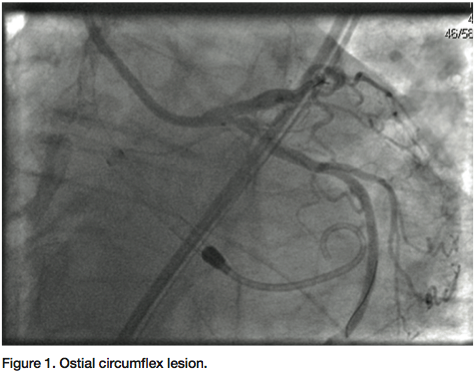

In order to adequately cover the ostium of his Cx, we had to ensure that a small portion of the deployed stent would have to protrude into the distal left main. To properly position the stent, and to avoid plaque shifting into the left main and the left anterior descending (LAD) coronary artery, we chose to employ a modification of the balloon backstop technique described in the past.4 Dual balloon inflation with one balloon inflated from left main into the LAD and the treating balloon inflated in the ostial Cx would create a large area of global ischemia, especially given the left dominant nature of the patient’s coronary anatomy. In order to effectively position both balloons without having to hastily perform the procedure, we chose to support the intervention with the Impella 2.5 circulatory support device.

a Judkins left 3.5 guiding catheter was used to engage the left main. Two 0.014” angioplasty wires were introduced; one into the LAD, and one into the distal Cx. A 3.0 x 12 mm balloon was placed in the ostium of the Cx, and a diagnostic angiogram was obtained (Figure 1). Subsequently, a 2.5 mm balloon was placed from the left main into the LAD. A 3.5 x 8 mm bare-metal stent was placed in the proximal Cx. The 2.5 mm balloon was inflated to 10 atmospheres, protecting the left main and proximal LAD from plaque shifting during deployment of the Cx stent (Figure 2). The stent in the Cx was then withdrawn until it indented the left main balloon. The balloon in the left main was inflated for nearly a minute during this process, and the patient was completely asymptomatic. Systolic blood pressure did drop from about 130 mmHg to about 90 mmHg, but diastolic pressure was maintained due to support from the Impella 2.5 circulatory support device. Both balloons were then simultaneously inflated for about 25 seconds (Figure 3). The patient transiently developed global ST elevation and systolic hypotension, but remained asymptomatic. After both balloons were deflated, final images revealed excellent coverage of the ostial Cx lesion, with no significant compromise of the left main and LAD. Intravascular ultrasound (IVUS) analysis after stent deployment revealed a cross sectional area of 6.3 mm2 in the ostium of the LAD, with excellent visualization of the Cx stent in the ostium. At the conclusion of the procedure, the Impella 2.5 circulatory device was weaned off in the cath lab, and the 13 French sheath was removed, with the pre-placed sutures securing hemostasis. The right femoral sheath was also secured using a single Perclose Proglide device. The patient was uneventfully discharged home the following morning.